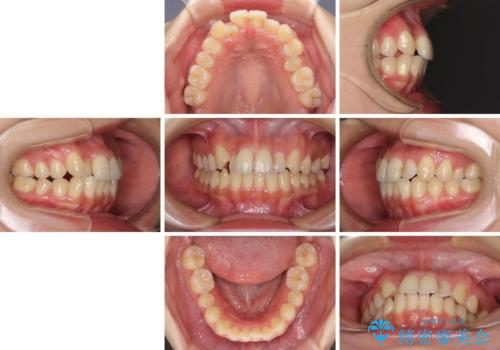

できる限り短い期間で終えたい ワイヤー矯正による咬み合わせの改善

- 前歯のデコボコを気にして来院された患者様です。

上顎右側犬歯が八重歯になっており、それによって奥歯が前方に移動しているため、右側の咬み合わせの改善が必要と判断されました。

マウスピース矯正では改善に時間がかかる、あるいは改善しきれない可能性があることを伝えたところ、短期間で確実に治療ができるワイヤー矯正を選択されました。

より治療を速やかに行うため、上顎右側にアンカースクリューを使用し、目標としていた1年半ほどで治療を終えることができました。